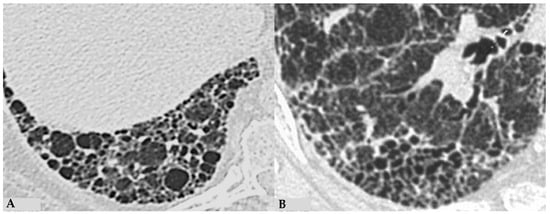

4. Pathologic Features of Fibrotic Hypersensitivity Pneumonitis

The insidious fibrotic counterpart of HP poses a diagnostic challenge in the ILD scenario from clinical, radiological and purely pathological perspectives. Diagnostic complexities arise partly from the myriad findings discernible in FHP, the divergences regarding defining characteristics of FHP and the chameleon-like nature of FHP to mimic other forms of fibrotic ILDs, particularly UIP/IPF. International guidelines advise against biopsy in clinically and radiologically defined UIP pattern cases. Biopsies are typically reserved for atypical/indeterminate forms. Importantly, a significant proportion of surgical and cryobiopsies in fibrotic ILD contexts correlate with FHP. Distinguishing fibrotic HP from UIP/IPF is not merely an academic exercise, as treatments significantly differ, especially since advanced forms of HP, exhibiting progressive features, do not benefit from corticosteroid treatment but may benefit from antifibrotic therapy. Fibrotic alterations in HP manifest in various forms: bronchiole-centric fibrosis, typically subpleural fibrosis, an NSIP-like fibrotic form and a UIP-like form. Granulomas and giant cells in FHP resemble those in non-HP but, unlike the latter, may exhibit ubiquitous distribution in lung parenchyma rather than being confined to peribronchiolar anatomy. A crucial pathological aspect concerning fibrosis in the evolving framework of HP is the classical “bridging fibrosis” appearance of peribronchiolar metaplasia, typically “air-centered” and better known as “bridging fibrosis”. This feature is generally a reliable pathological marker of FHP, usually affecting a substantial number of bronchioles (>50%). However, occasional foci of peribronchiolar metaplasia may be found in any fibrotic interstitial pneumonia and even in otherwise normal lungs. Therefore, determining the proportion of affected bronchioles is necessary for using this characteristic in FHP diagnosis. Granulomas and giant cells are valuable when present, as are infiltrates and lymphocyte aggregates; however, they are found only in a minority of FHP cases (Figure 11). “End-stage lung” findings with honeycombing indicate a UIP pattern, necessitating correlation with historical, clinical, functional and radiological data, and sometimes pathological data, to provide conclusive information about a specific disease, as isolated findings only signify progressive and final fibrotic damage (Figure 12A). Granulomas/giant cells are similar to those found in NFHP, but unlike the latter, they can be found anywhere in the parenchyma and not just in a peribronchiolar position. Moreover, they are highly useful when present; however, they are found only in a minority of FHP cases. In the differential diagnosis, granulomas and giant cells can occasionally be found in CTD-ILDs or even in other non-necrotizing chronic granulomatous diseases such as sarcoidosis but are not part of pathological alterations seen in UIP/IPF forms [17,18,19]. As in NFHP, Schaumann bodies are occasionally present and serve as substitutes for granulomas (Figure 12B). The interstitial inflammatory infiltrate of FHP may be scanty, as in UIP/IPF, or moderately “cellular,” primarily composed of lymphocytes with a variable number of plasma cells and occasionally some eosinophils when present. Foci of fibroblasts are common in FHP and potentially analogous in pathological configuration to those found in idiopathic forms (UIP/IPF), although often numerically fewer than in idiopathic pathologies such as IPF, and may be associated with isolated peribronchiolar fibrosis. It has also been postulated that fibroblast foci associated with peribronchiolar fibrosis reliably point towards a diagnosis of FHP rather than UIP/IPF diagnosis [20,21]. The differential diagnosis of FHP includes some chronic evolution forms of sarcoidosis, aspiration pneumonitis, collagenopathy-related ILDs, some forms of NSIP and even some clinical-radiological and pathological forms of Interstitial Pneumonia with Autoimmune Features (IPAF). In any case, it is crucial to emphasize that the diagnosis of each ILD is an integrated multidisciplinary process, where each piece must be precisely analyzed by dedicated specialists (pulmonologist, radiologist, pathologist, rheumatologist). Only through the correct interaction of the MDT elements can a coherent and sometimes conclusive diagnosis be achieved.

Figure 11.

FHP: diffuse fibrotic change with lymphocytic infiltration and giant cells ((A): hem-eo 20×); FHP with predominantly airway-centered inflammation characterized by peribronchiolar metaplasia, foamy macrophages in alveolar spaces, poorly formed granulomas and giant cells ((B): hem-eo 40×).

Figure 12.

FHP: diffuse fibrotic change with prominent peri-bronchial fibrosis in UIP pattern that is against a diagnosis of UIP/IPF and, according to anamnesis and clinical data, is typical for UIP in FHP (A). Schaumann body. Schaumann bodies serve as the equivalent of granuloma tombstones, offering identical diagnostic insight (B).